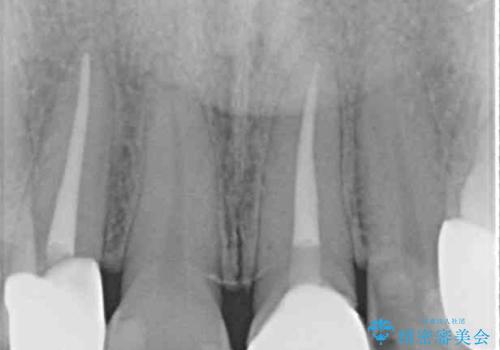

途中通院されなかった時期が何度かあったため、初診から4年以上の年月がかかりましたが、比較的スムーズに治療を進めることができました。

下顎前歯の歯列を整えたことで、上顎前歯の咬み合わせが安定し、自然な口元に仕上げることができました。